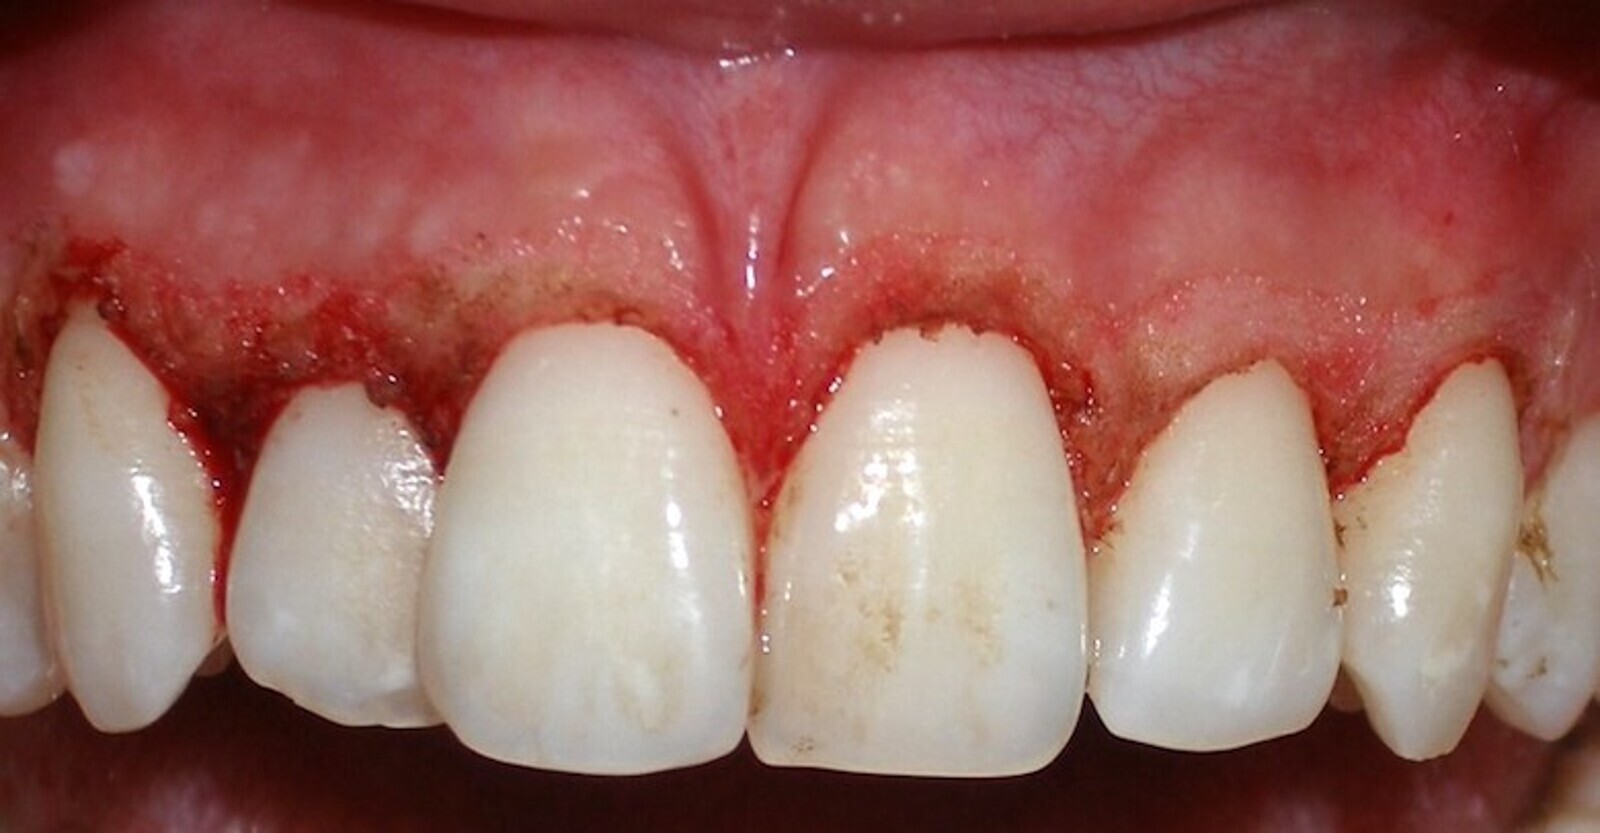

En la cirugía de tejidos blandos, la gingivectomía es probablemente uno de los tratamientos más básicos y que más frecuentemente se realizan en periodoncia quirúrgica (Figuras 17-19). Realizar una gingivectomía con láser es un procedimiento muy sencillo y a la vez bastante rápido que produce un efecto inmediato y que, comparado con una gingivectomía convencional con bisturí, ofrece una serie de ventajas como por ejemplo una hemostasia excelente, lo que mejora la visibilidad del campo y resulta en una molestia postoperatoria mínima para el paciente11.

La gingivectomía con láser es un procedimiento muy rápido y sencillo que ofrece beneficios comparado con una gingivectomía convencional (ver Figuras 17-19).

Fig. 17.

Fig. 18.

Fig. 19. Las figuras 17-19 muestran que la gingivectomía con láser es un procedimiento muy rápido y sencillo que produce un efecto inmediato y ofrece ventajas comparado con la gingivectomía convencional con bisturí.